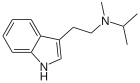

| MiPT | artificial | H | CH3 | CH(CH3)2 | N-Methyl-N-isopropyltryptamine | 96096-52-5 |

| DiPT | artificial | H | CH(CH3)2 | CH(CH3)2 | N,N-diisopropyltryptamine | 14780-24-6 |